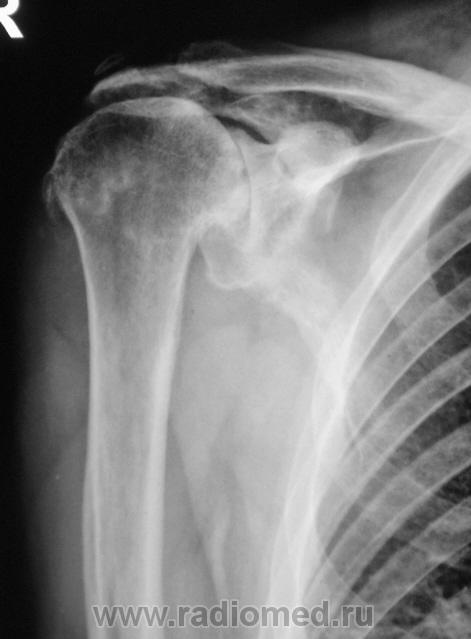

Двусторонний деформирующий остеоартроз: справа усилен верхним подвывихом с образованием неартроза с акромиальным отростком.

2-сторонний ДОА, справа подвывих, неоартроз + калькулезный (известковый) бурсит(возможно тоже 2-сторонний)

В левом суставе - вероятно изменения за счёт артроза, обызвествления связок

В правом - последствия травмы (подвывих, перелом головки?)